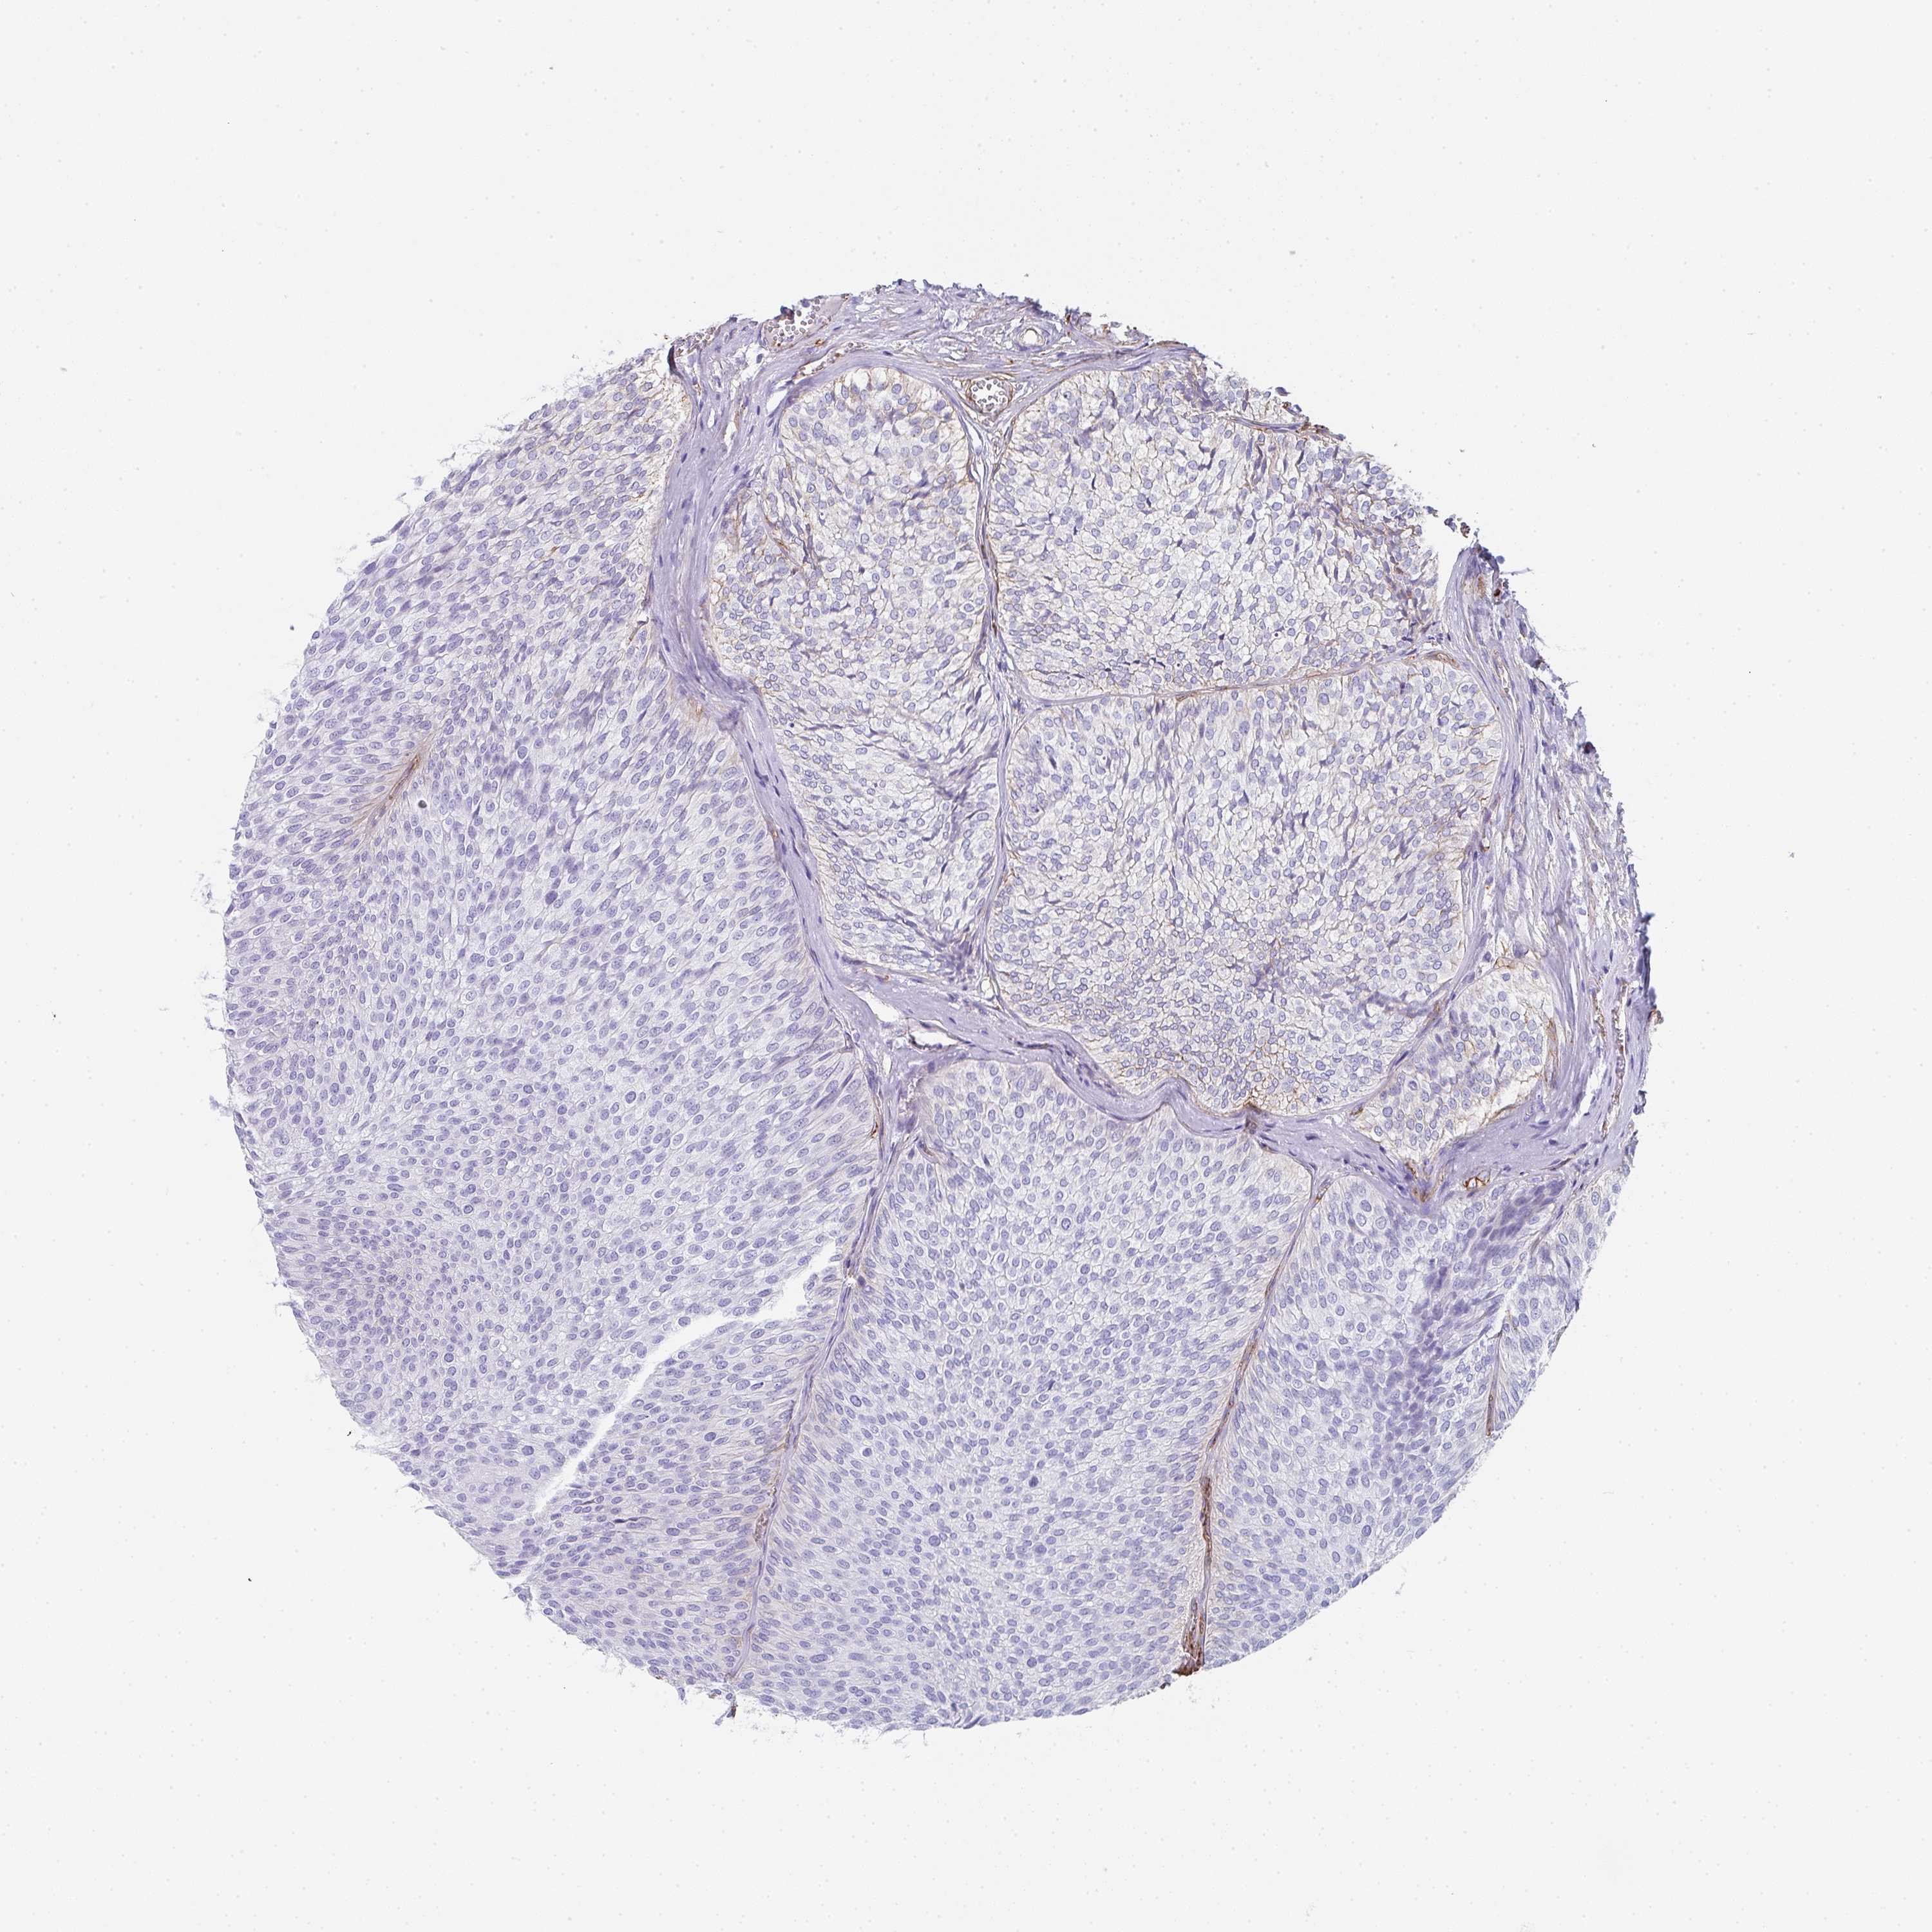

UROTHELIAL CANCER - Protein expressioni

A mouse-over function shows sample information and annotation data. Click on an image to view it in a full screen mode. Samples can be filtered based on level of antibody staining by selecting one or several of the following categories: high, medium, low and not detected. The assay and annotation is described here.

Antibody stainingi

Antibody staining in the annotated cell types in the current human tissue is reported as not detected, low, medium, or high, based on conventional immunohistochemistry profiling in selected tissues. This score is based on the combination of the staining intensity and fraction of stained cells.

Each image is clickable and will lead to virtual microscopy that enables deeper exploration of all samples and also displays staining intensity scores, fraction scores and subcellular localization as well as patient and tissue information for each sample.

Antibody HPA051452

Antibody HPA056940

Staining

High

Medium

Low

Not detected

Intensity

Strong

Moderate

Weak

Negative

Quantity

>75%

75%-25%

<25%

None

Location

Nuclear

Cytoplasmic/membranous

Cytoplasmic/membranous,nuclear

Urothelial carcinoma, High grade

Urothelial carcinoma, Low grade